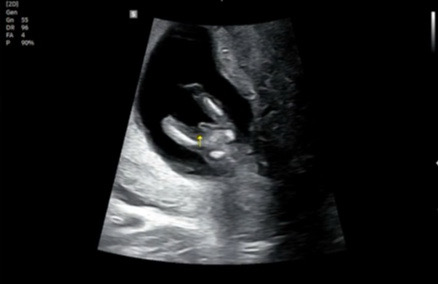

12주 6일인데 성별 알았네요 ㅎㅎ

초음파 보는 중에 애기가 보여줘서 빨리 성별을 알았네요ㅋㅋㅋㅋ 표시해주신 선생님ㅋㅋ

남자아기예요??

네 ㅋㅋㅋ